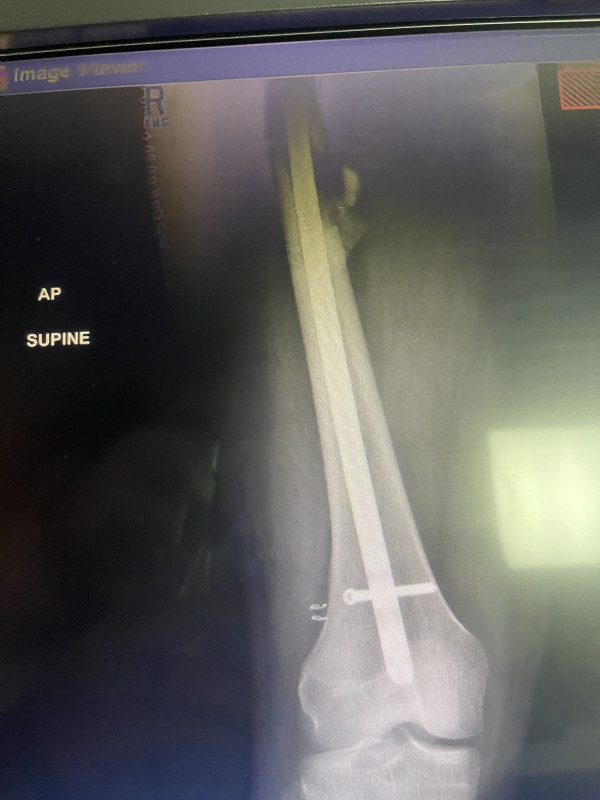

Hello, my son was in a motorcycle accident and broke his femur. Thankfully he was wearing his helmet or this would be a totally different situation. He is a young man so recovery is hopeful with many many months of physical therapy. The healing process for a broken femur is not a quick one. He will be unable to work for quite awhile. Medical bills and physical therapy help would be much appreciated. Thank you for your time.